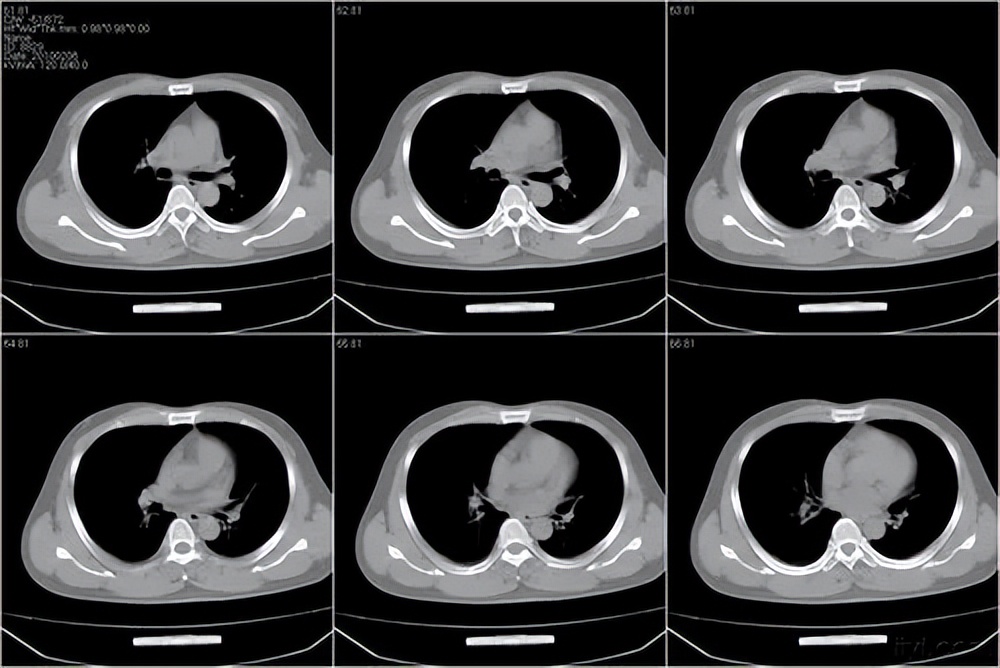

双肺像撒了一把沙子一样,上叶、下叶到处都是磨玻璃结节!

好在通过对其肺CT影像的对比观察发现,虽然双肺密密麻麻的都是磨玻璃结节,数量极多,但真正比较大的主病灶只有两个,一个直径12.5mm,一个8.5mm,且与两年前对比,变化不明显。可见,虽然患者本身问题比较严重,但是目前尚未对身体健康构成危险,采取规范治疗随访即可。